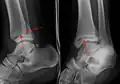

A specialized AP stress view of the ankle is performed when there is concern for an unstable ankle injury. There are two types of stress views: gravity and mechanical.[10] In the gravity stress view, the patient lies in the lateral decubitus position with the ankle dangling over the edge of the table to mimic the mechanical stress view.